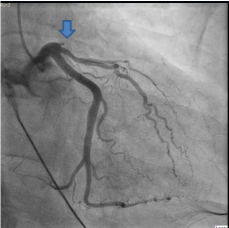

Patient was taken for emergent cardiac catheterization that showed 100% stenosis in proximal left anterior descending artery with TIMI 0 flow (Figure 2 and 3). There were abundant collaterals from RCA to septum (Figure 4). Due to late presentation MI with Q waves on EKG, PCI was deferred. Patient was started on aspirin, clopidogrel, carvedilol, high-intensity statin and unfractionated heparin and was admitted to coronary care unit for further management and observation.

Figure 3. Coronary Angiogram in Right Anterior Oblique (RAO) Cranial view with complete occlusion of LAD as indicated by arrow